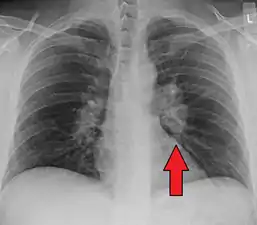

Chest radiograph changes are divided into four stages:[105]

- bihilar lymphadenopathy

- bihilar lymphadenopathy and reticulonodular infiltrates

- bilateral pulmonary infiltrates

- fibrocystic sarcoidosis typically with upward hilar retraction, cystic and bullous changes

Although people with stage 1 radiographs tend to have the acute or subacute, reversible form of the disease, those with stages 2 and 3 often have the chronic, progressive disease; these patterns do not represent consecutive "stages" of sarcoidosis. Thus, except for epidemiologic purposes, this categorization is mostly of historic interest.[28]

Hilar adenopathy especially on the person's left (AP CXR)

Hilar adenopathy especially on the person's left (lateral CXR)

Hilar adenopathy especially on the person's left (coronal CT)

Hilar adenopathy especially on the person's left (transverse CT)